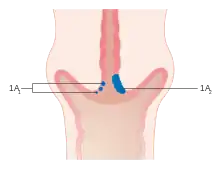

The location of cervical cancer can be described in terms of quadrants, or corresponding to a clock face when the subject is in supine position.